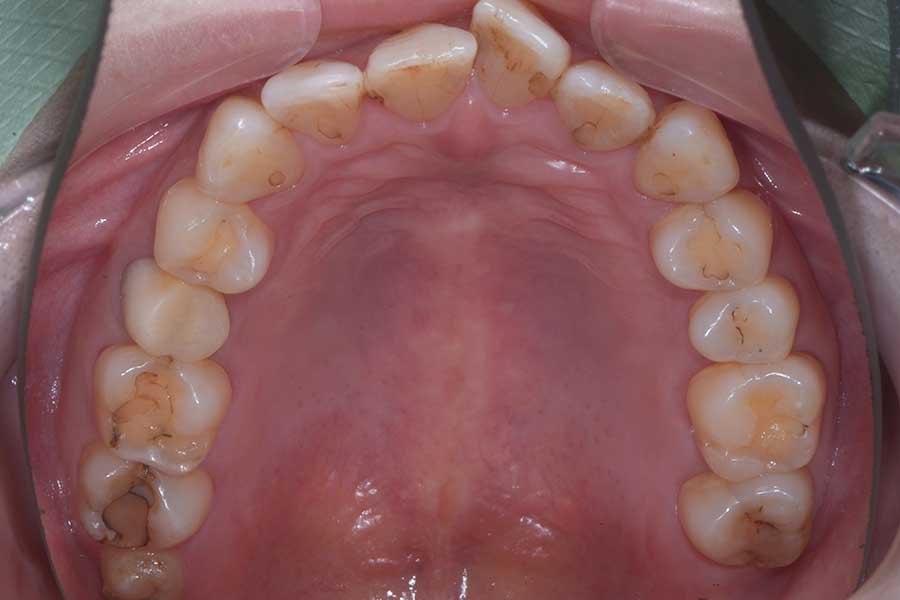

治療前

主訴 前歯の虫歯治療の前に飛び出た前歯を引っ込めたい

治療内容 上顎ラビアル矯正(表側矯正)